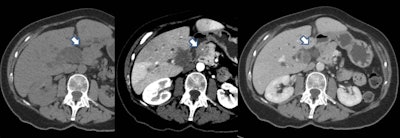

On two scans taken six months apart, a pancreatic tumor (stage IVB) was missed. On the MRI for renal cancer restaging six months prior, the lesion in the tip of the pancreatic tail was small and visible in retrospect only. Figure courtesy of Dr. Nosheen Umar.Umar presented the group's preliminary findings at the United European Gastroenterology (UEG) Week, which is being held in Vienna from 8 to 11 October. The analysis revealed over one-third (36%) of the PIPC cases were potentially avoidable, she said.